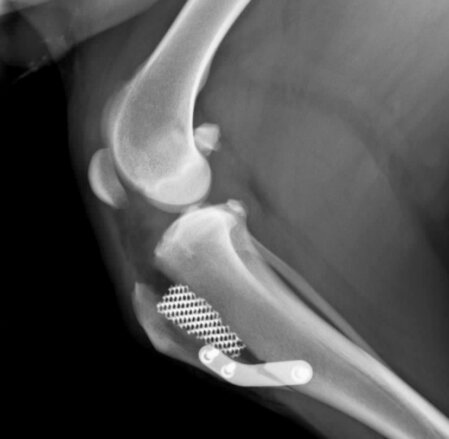

La TTA porosa (Tibial Tuberosity Advancement Porous) è una tecnica chirurgica utilizzata per il trattamento della rottura del legamento crociato craniale nel cane.

Si tratta di un’evoluzione della tecnica TTA tradizionale, che prevede l’utilizzo di impianti in titanio poroso: questo materiale favorisce una migliore integrazione ossea e una guarigione più stabile e rapida.

La TTA non “sostituisce” il legamento crociato, ma riconfigura la biomeccanica: avanzando la tuberosità tibiale, l’angolo del tendine del quadricipite/patellare rispetto al plateau tibiale (Patellar Tendon Angle, PTA) viene portato attorno a 90° in carico, riducendo la componente di taglio craniale e stabilizzando dinamicamente l’articolazione.

La maggior parte dei pazienti ottiene ripresa funzionale buona-eccellente entro 8–12 settimane. Dolore e zoppia regrediscono progressivamente. Iproprietari spesso riferiscono ritorno all’attività pre-lesione. Esiti inferiori possono essere legati a: obesità, meniscopatia, non aderenza al protocollo riabilitativo, comorbilità ortopediche (anca/colonna).

Quanto dura l’intervento? 60–90 minuti medi, dimissione in 24 h se stabile.

Quando camminerà senza zoppia? Miglioramento già in 1–2 settimane; ritorno quasi completo in 8–12 settimane.

Gli impianti restano; si rimuovono solo se indicato (es. infezione/irritazione).

Il cane potrà correre/saltare? Sì, gradualmente dopo il via libera clinico e RX di controllo.